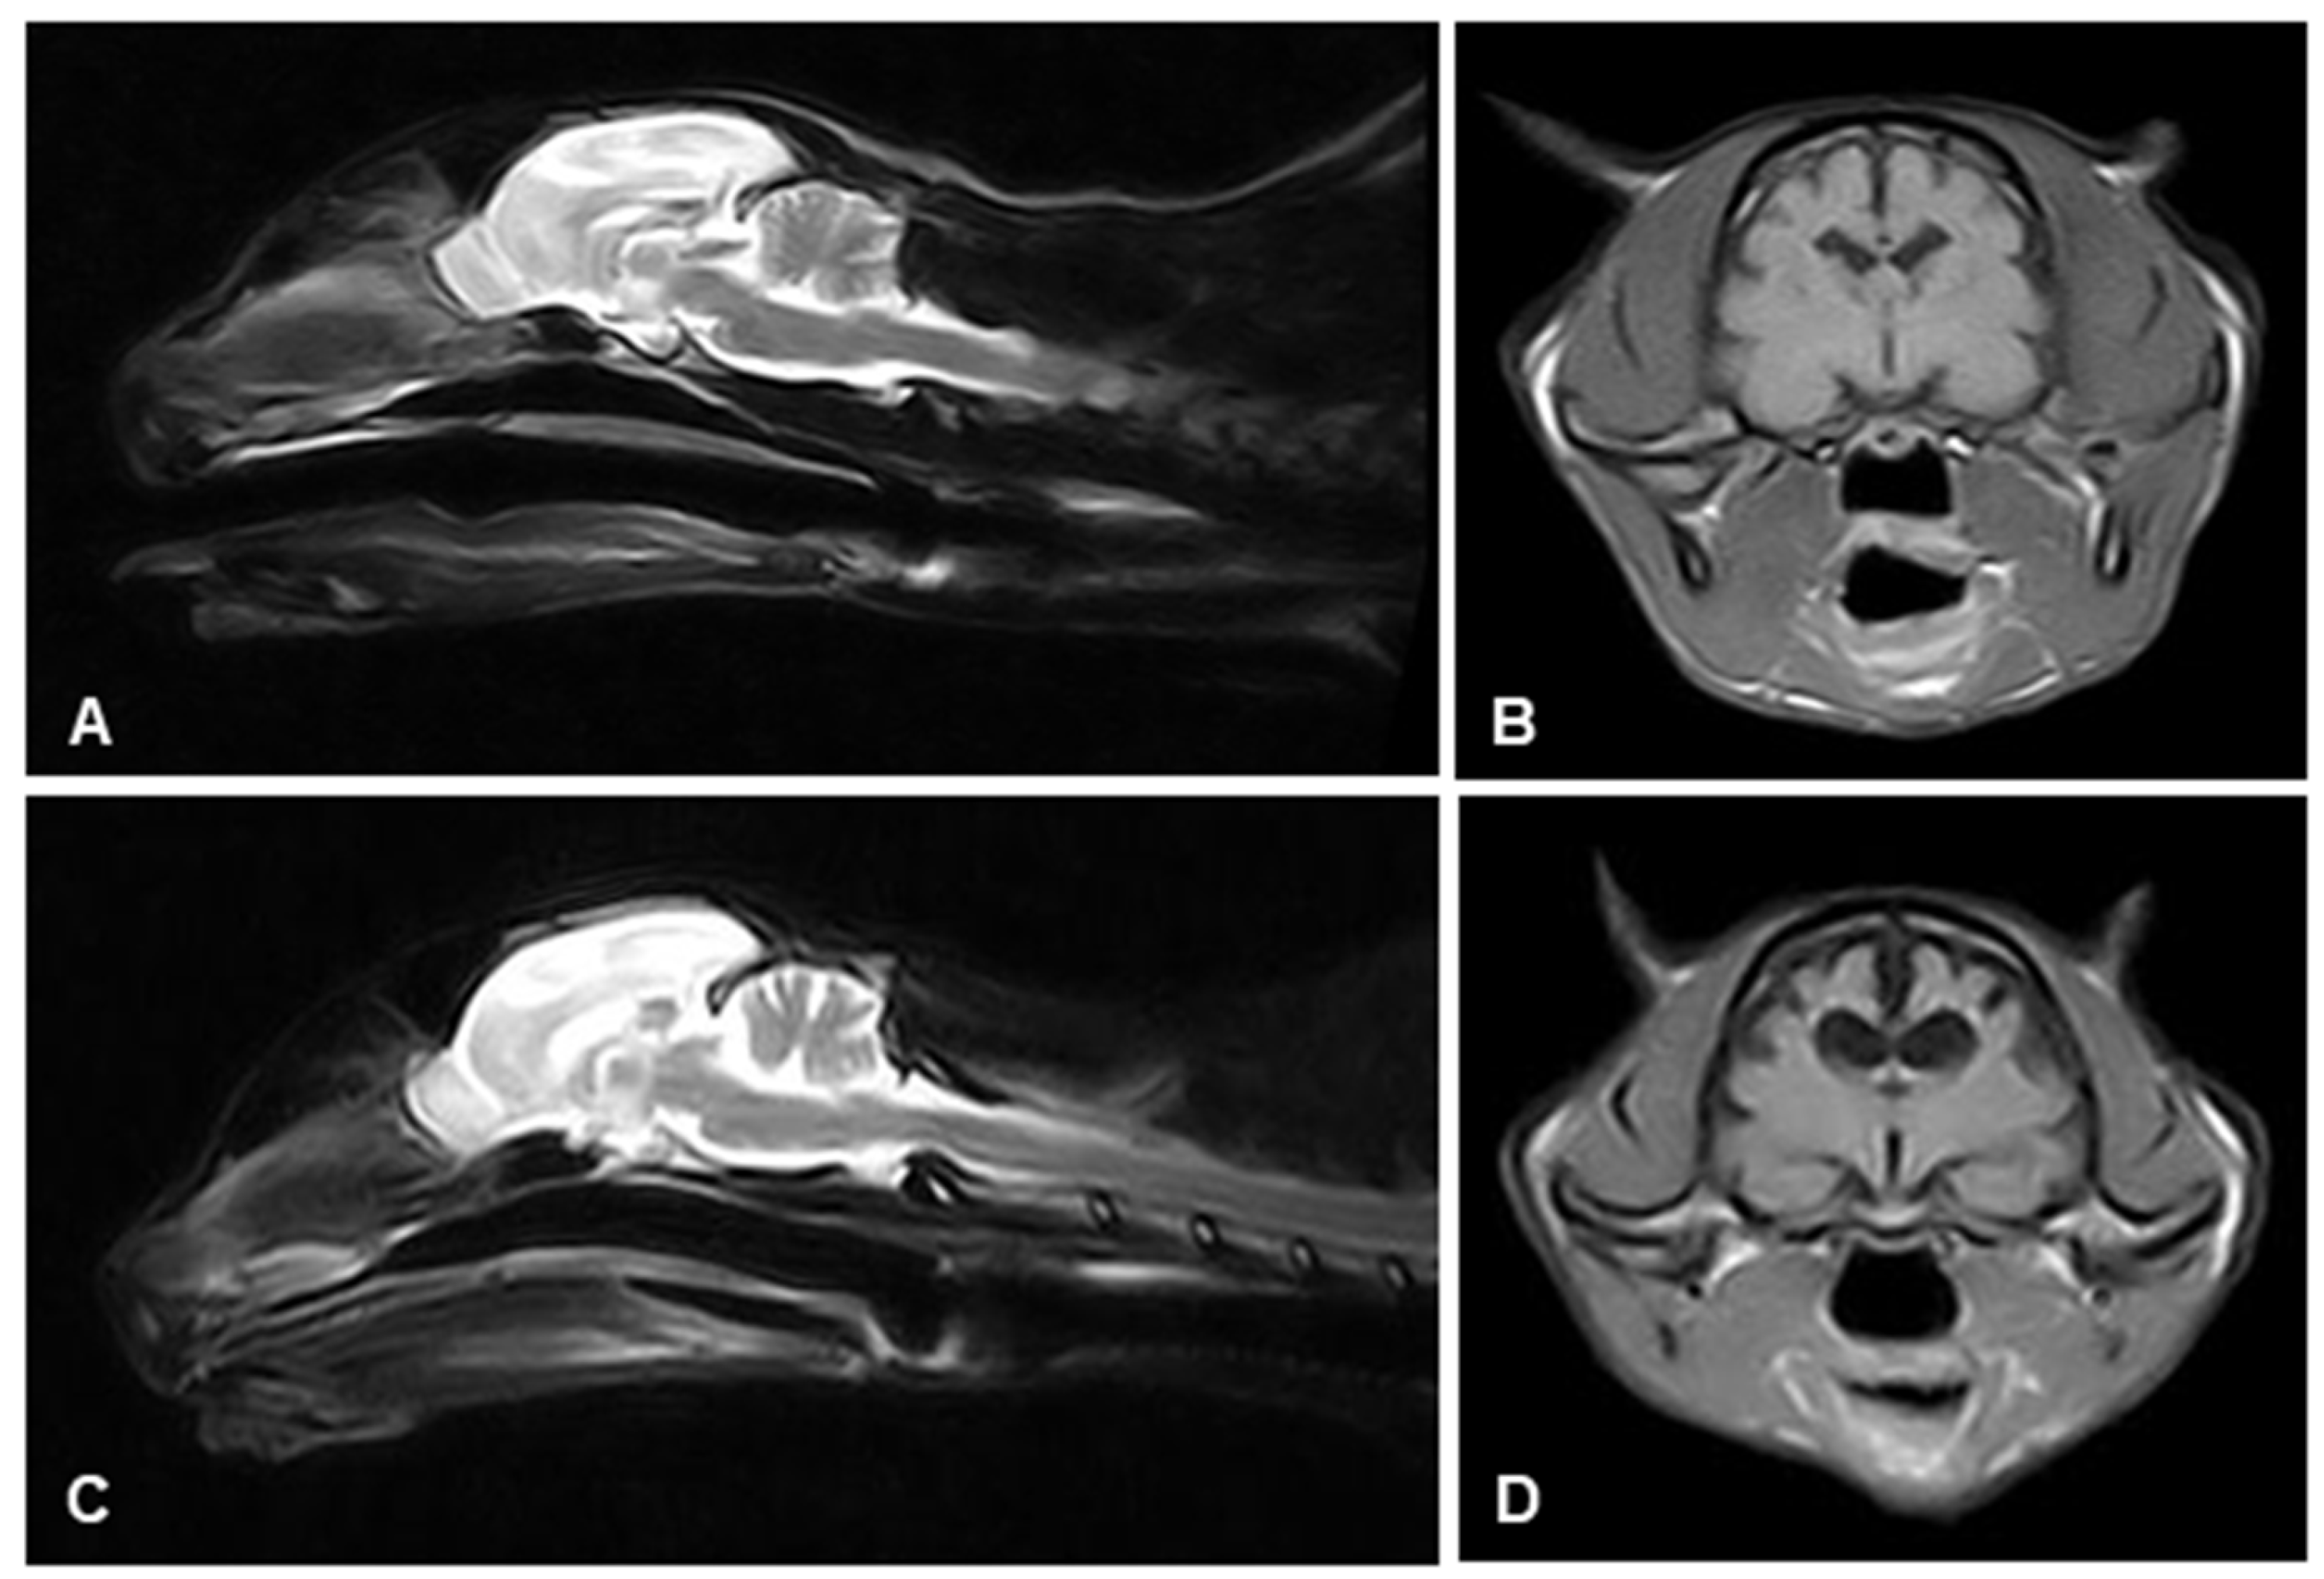

2.2. Magnetic Resonance Imaging (MRI)